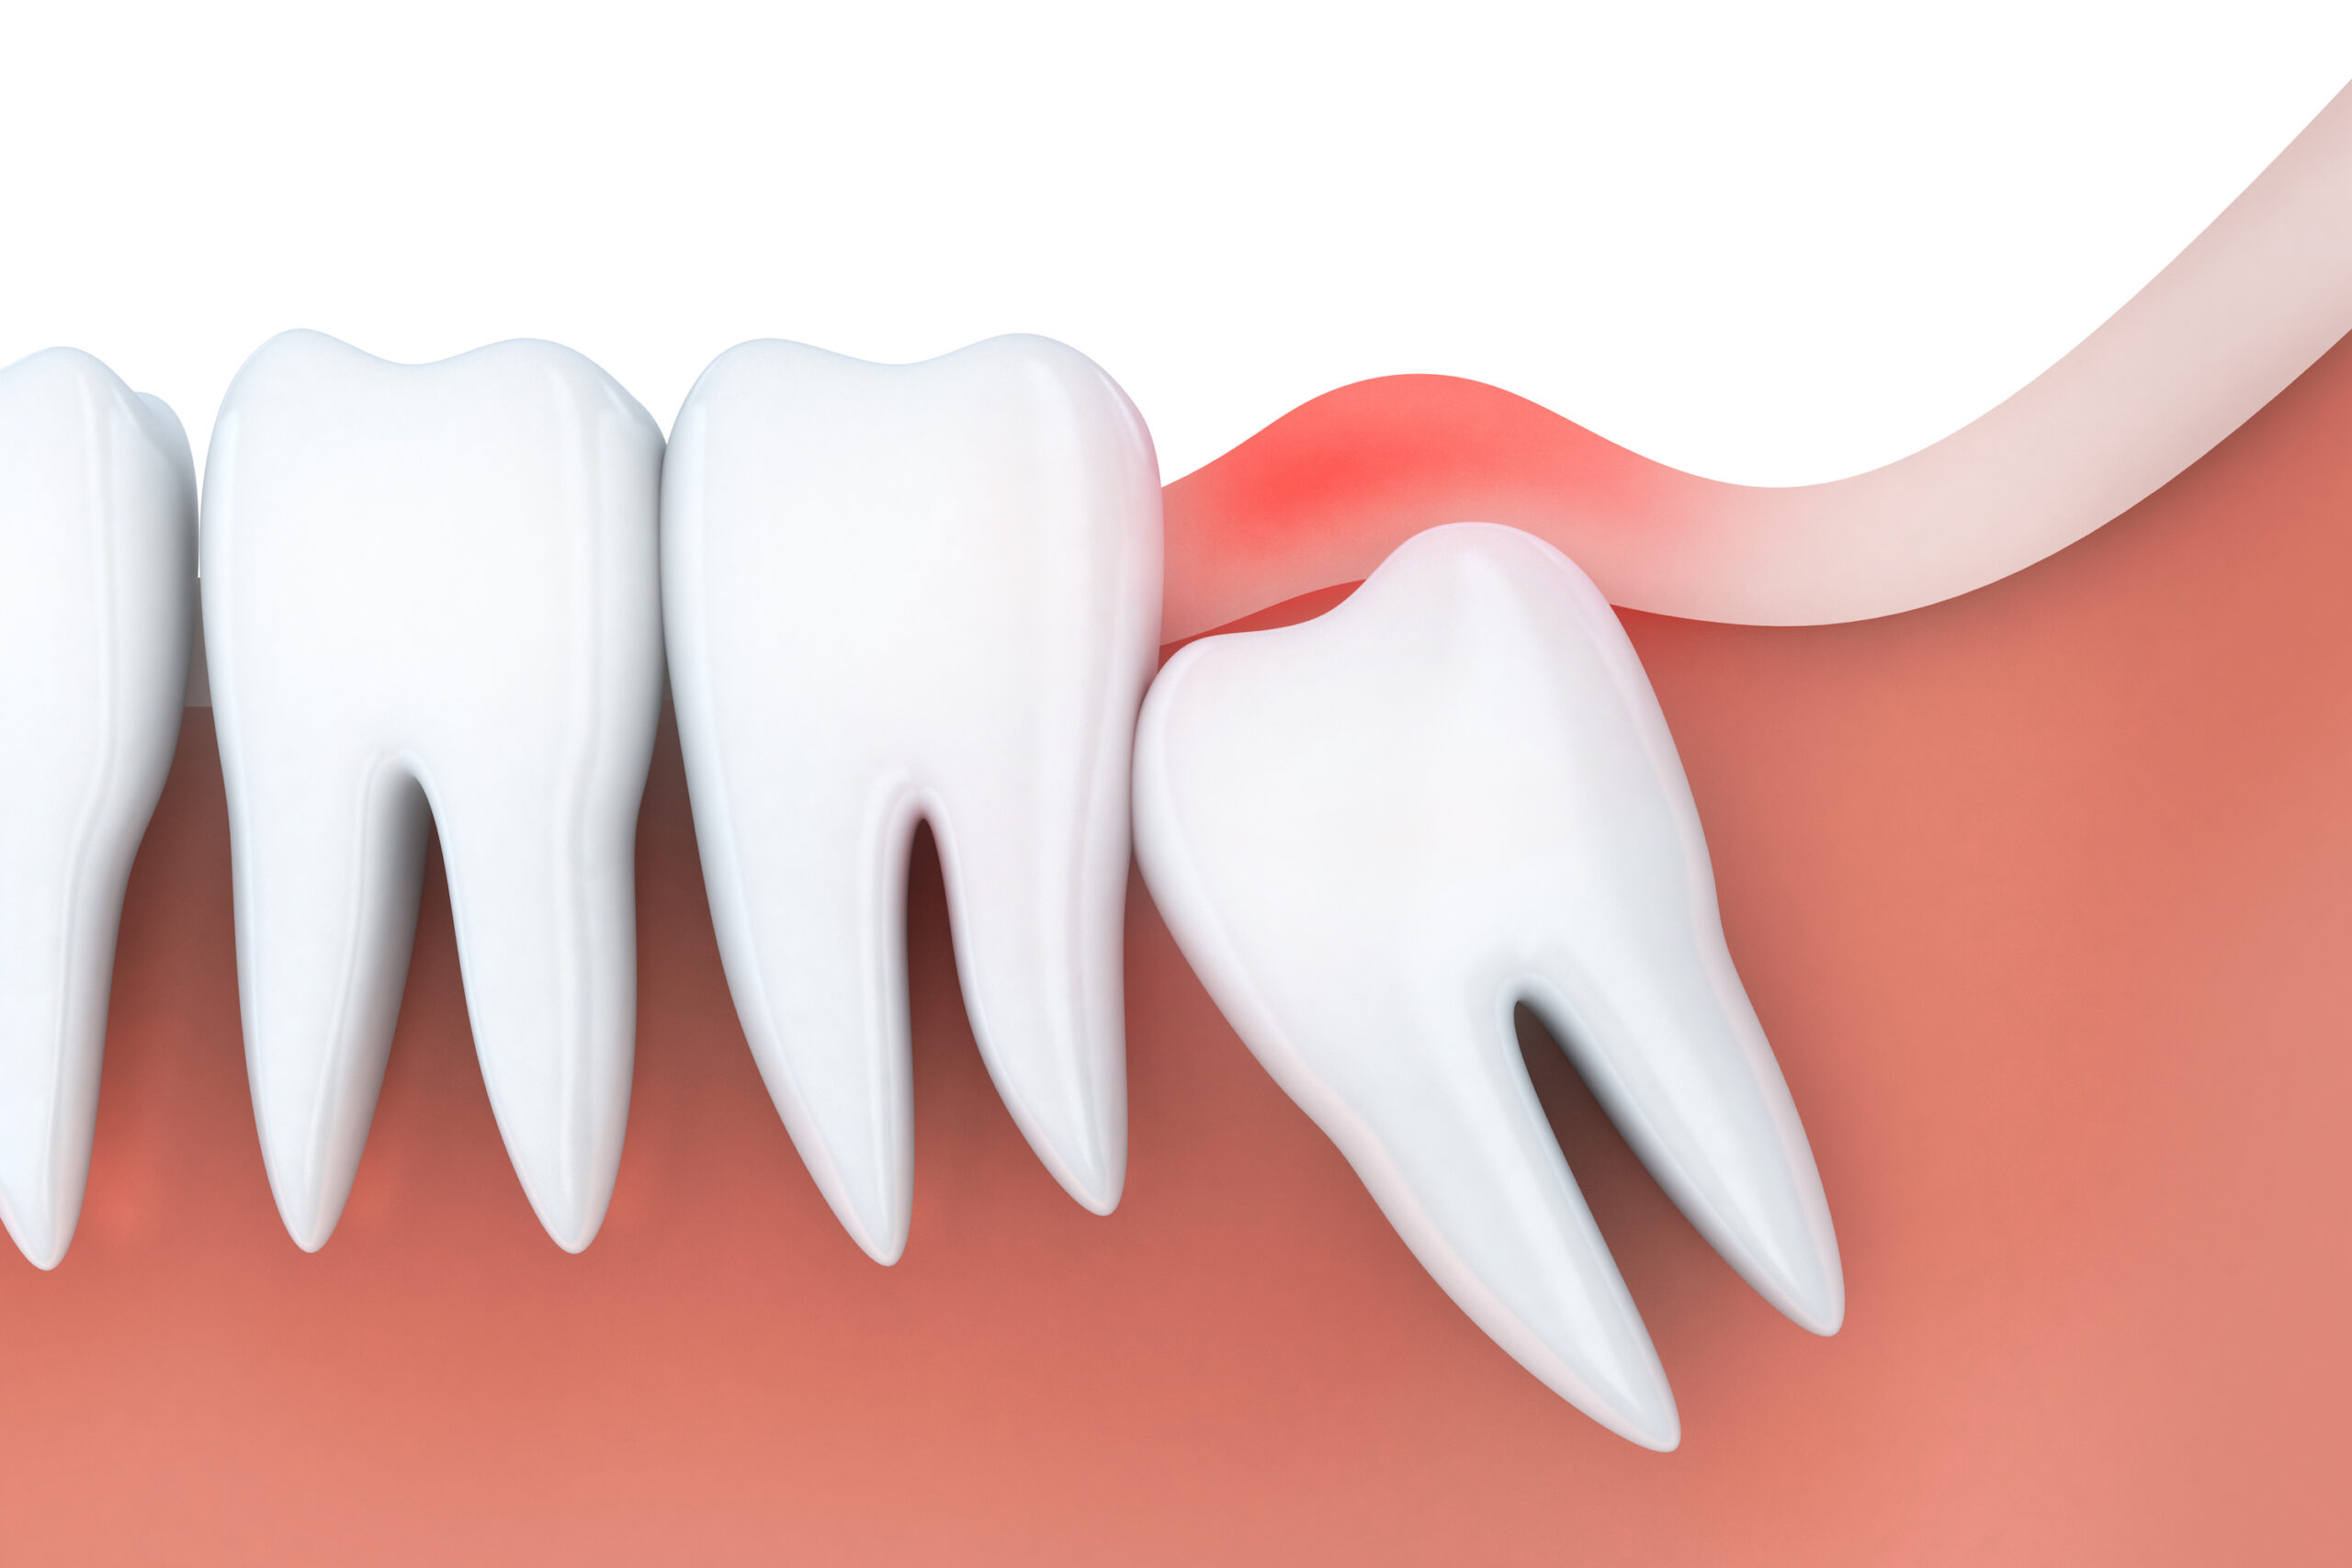

あごの骨の中で親知らずの向きや位置がずれていると、斜めや横向きに生えたり、歯ぐきから一部だけ見えている半埋伏の状態になったり、完全に骨の中に埋まったままの完全埋伏になったりします。

生え方や位置が悪い場合

あごの骨の中で親知らずの向きがずれていると、斜めや横向きに生えてきたり、途中で止まってしまったりします。まっすぐ生えるスペースが足りないため、手前の奥歯を強く押したり、歯ぐきを内側から突き上げたりして、鈍い痛みや圧迫感が出ます。

下の親知らずは特に、あごの骨が細くてスペースが不足しやすく、歯ぐきの一部だけを破って生えてくることがあります。このような半埋伏の状態では、歯ぐきが繰り返し傷つき、炎症や腫れを起こしやすくなります。

親知らずが途中までしか生えていないと、歯ぐきとの間に小さなポケットのようなすき間ができます。このすき間に食べかすや細菌が入り込むと、親知らずの周囲に炎症が起こり、智歯周囲炎と呼ばれる状態になります。

智歯周囲炎では、親知らずの周りの歯ぐきが赤く腫れ、押すと強い痛みを感じます。症状が進むと、口が開けにくくなったり、飲み込むときに痛みが出たり、あごの下や首のリンパ節が腫れて熱っぽくなることもあります。